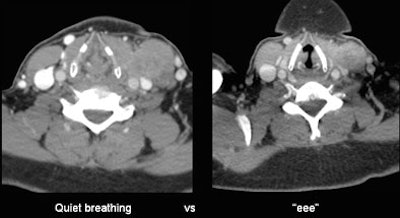

| In a patient with a history of superglottal squamous cell carcinoma, CT images acquired with a modified Valsalva breath-hold maneuver (left) closed the airway, leaving the radiologists unable to rule out a pyriform sinus mass. At right, CT acquired with the "eee" phonation showed there was no tumor. Had the "eee" technique been used initially, the PET exam (far right) would have been unnecessary. All images courtesy of Dr. Megan Strother. |

For example, in a patient with a history of squamous cell carcinoma, using the "eee" technique during the scan would have rendered PET unnecessary to rule out a pyriform sinus mass. The patient whose CT images were acquired with a modified Valsalva technique showed suspiciously asymmetric soft tissue in the region, Strother said. The group ordered PET, and eventually acquired the images again with MDCT using the "eee" technique and a breath-hold, which depicted the anatomy clearly.

"Several thousand dollars later you've got a normal PET and everybody breathes better," Strother said. "The point is we would have hoped to bypass the PET scan."